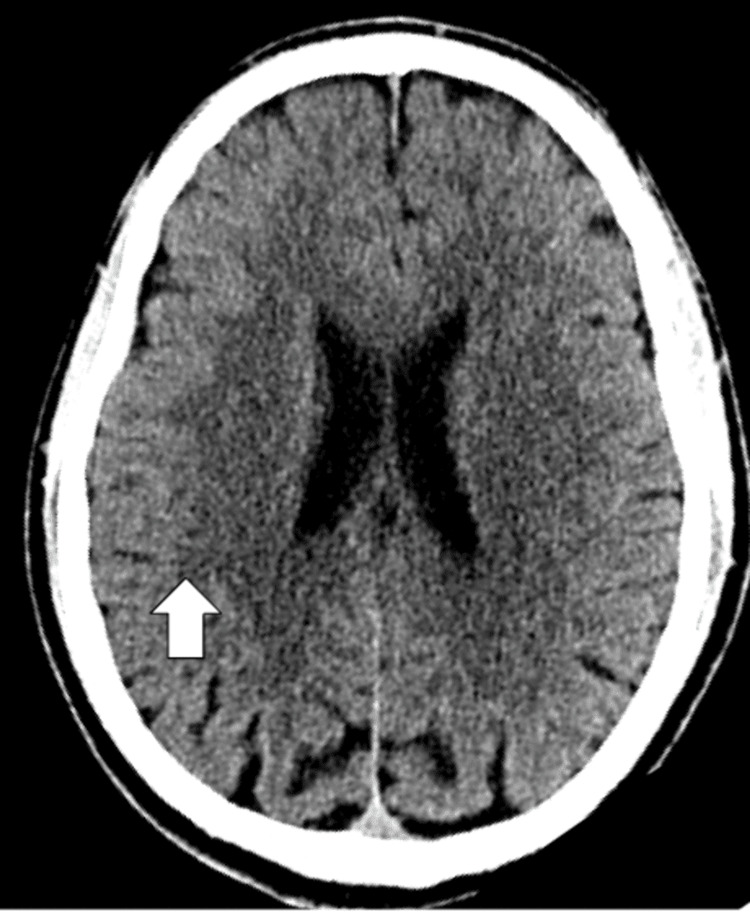

In addition, an EKG and CT scan of the head were done to rule out any organic causes for the patient’s presentation. The EKG is shown in Figure 1, normal sinus rhythm with a ventricular rate of 79 beats per minute with a QTc of 410 milliseconds, and no signs of arrhythmias or myocardial infarctions. The CT of the head without contrast demonstrated in Figure 2 shows no signs of an acute infarct or intracranial hemorrhage, with mild cerebral atrophy.